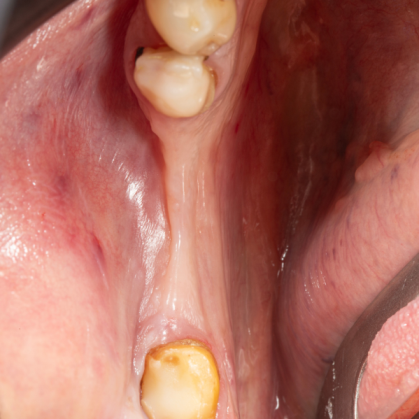

İmplant etrafındaki kemik açıklığını kemik grefti ile tedavi ettiğimiz vakamız